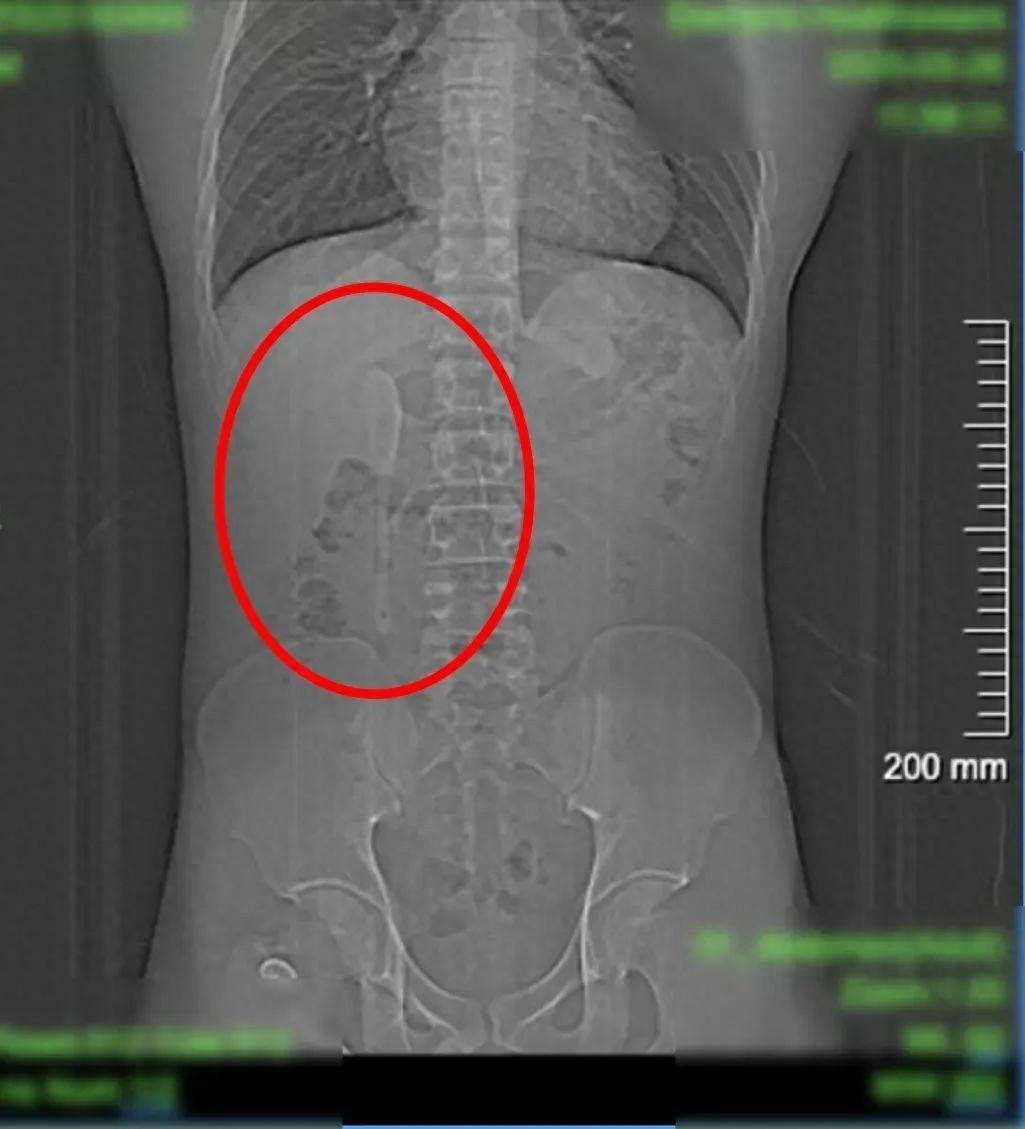

CT显示这支近15厘米长勺状物体

严丝合缝地横亘于

十二指肠球部与降部交界的生理狭窄处

稍有不慎即可能刺穿肠壁

引发腹膜炎或大出血